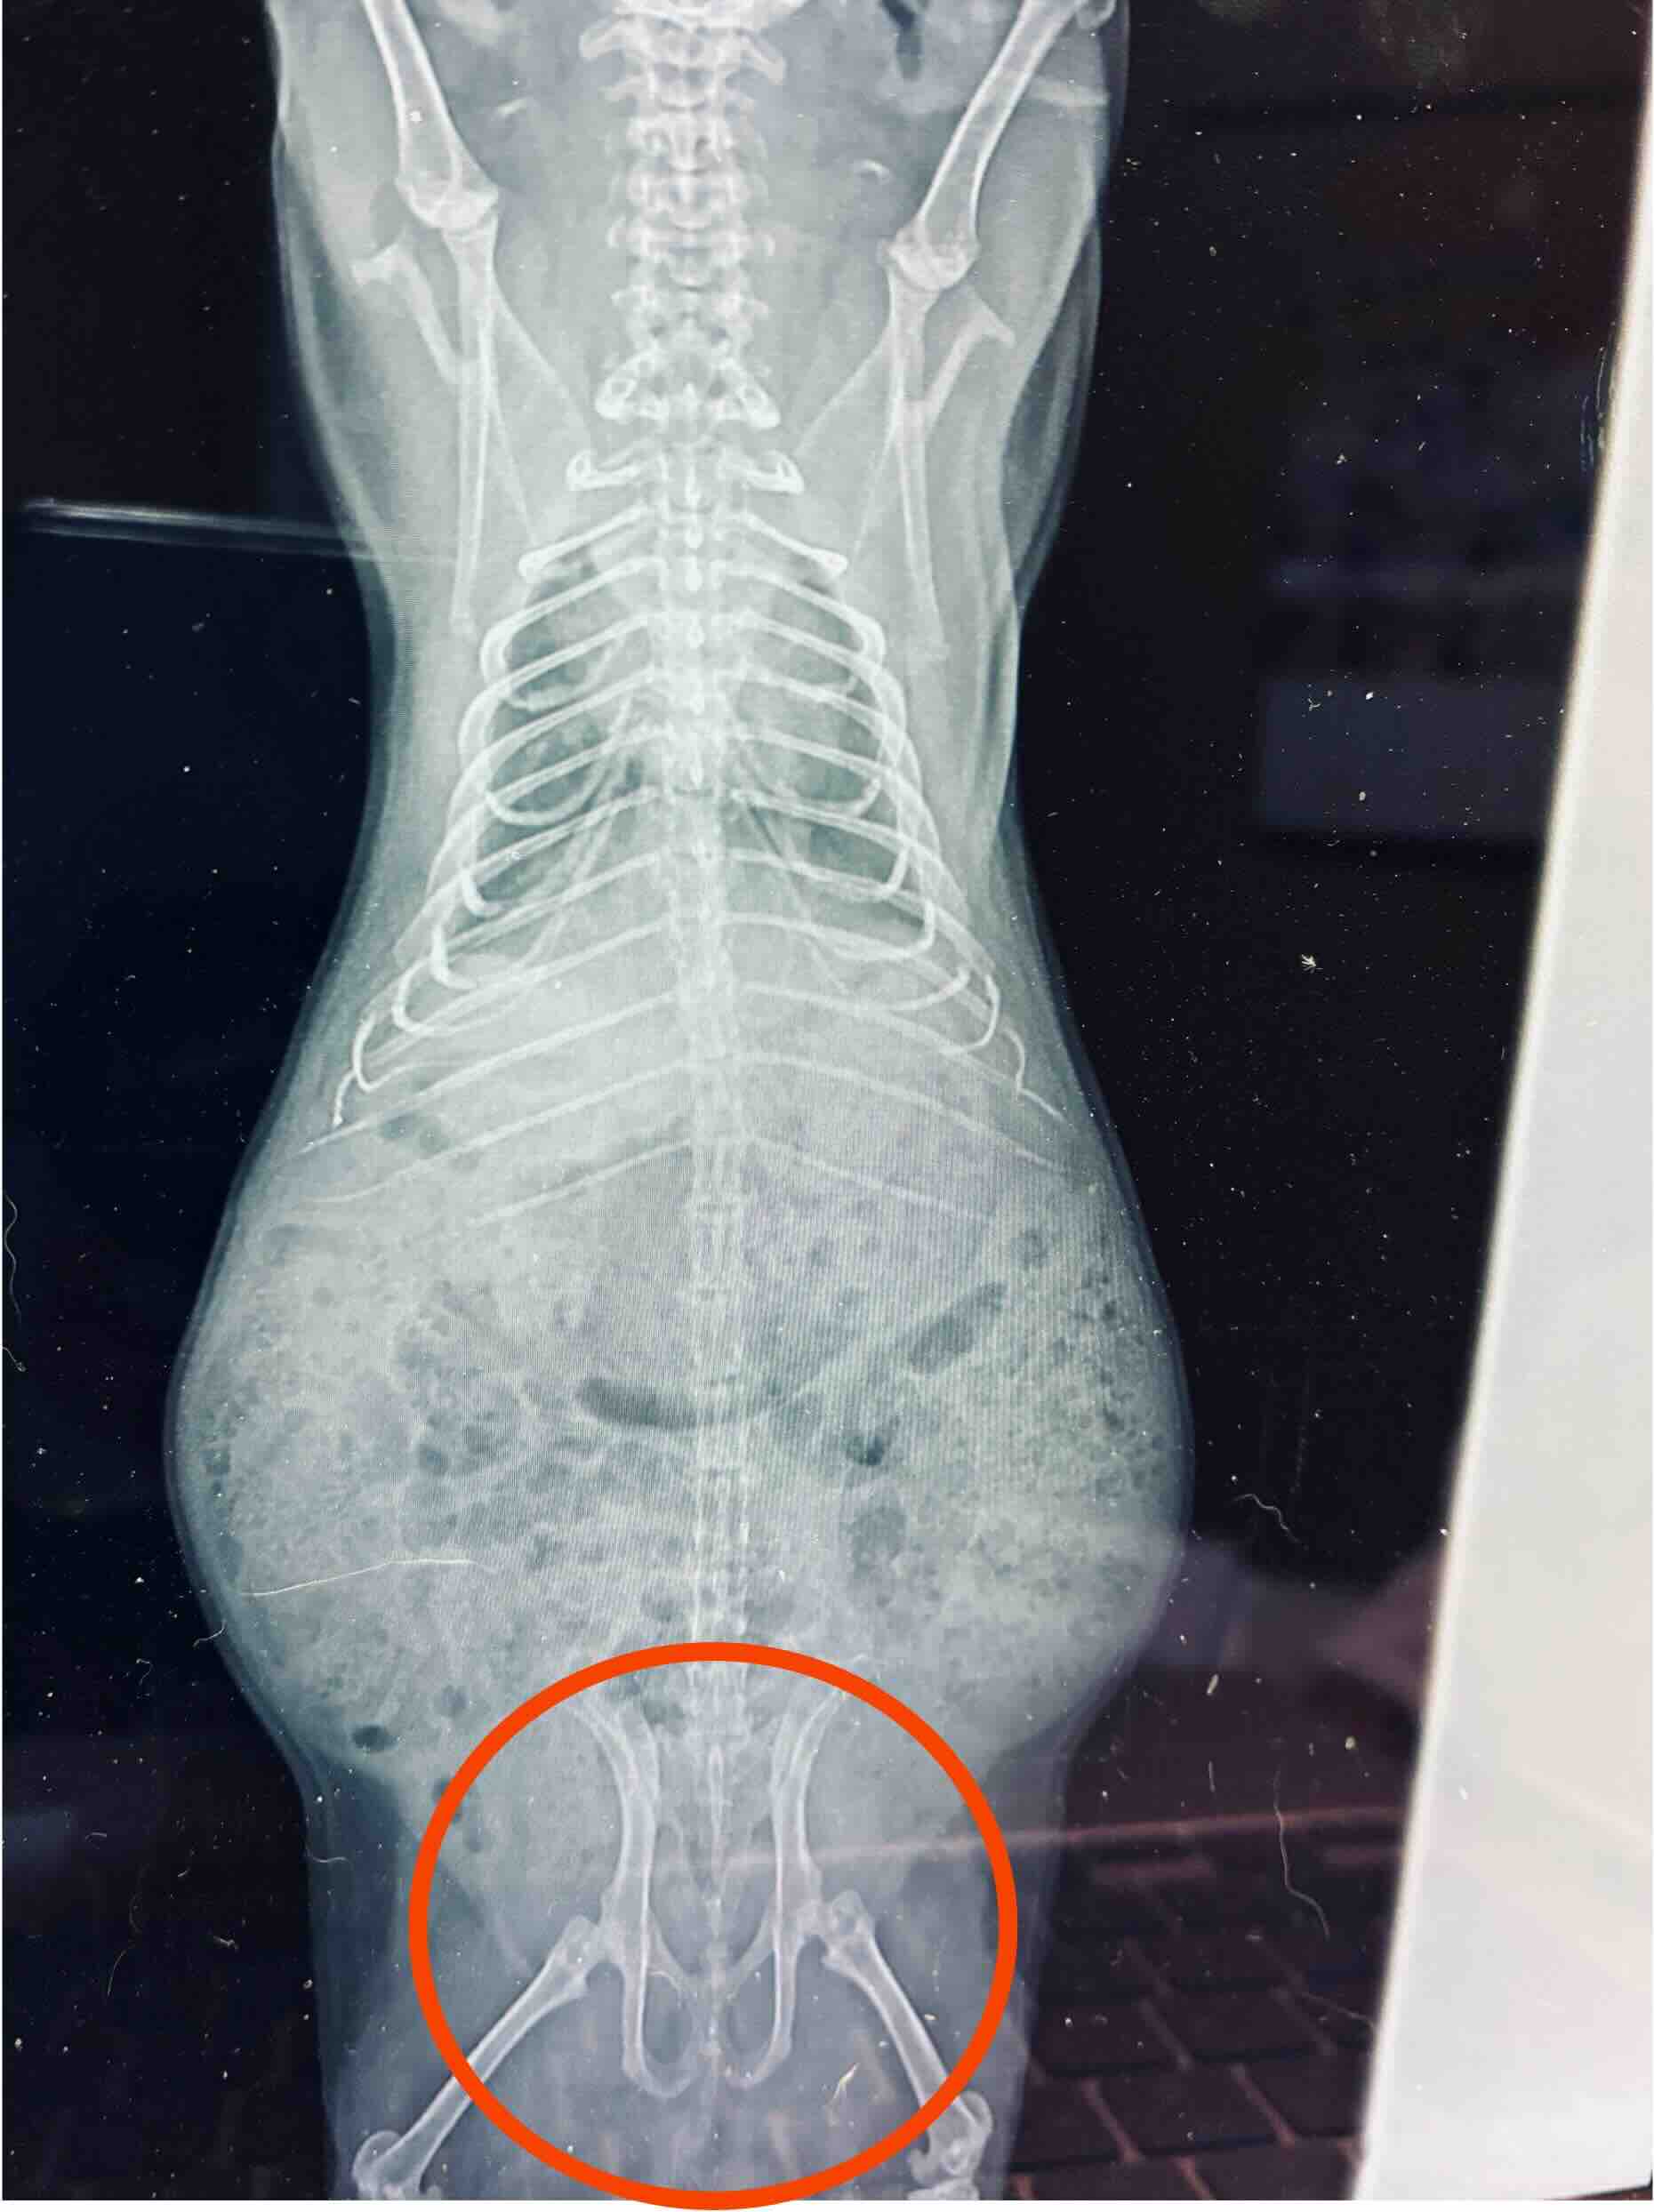

尿路に結石は見当たらなかった。泌尿器系あるいは生殖器系のどこかに問題あるはずだが、尿サンプルがないので確実なことはわからないようだ。 季節によっては(?)発情期(マーキング時)に出血を伴うこともあるそうで、これに該当するのかもしれないし、他の泌尿器・生殖器系に疾患があるのかもしれないと言われた。 ただし、

| X線検査(読影、診断料) | 2,200 |

| X線検査(四切) | 2,750(×2) |